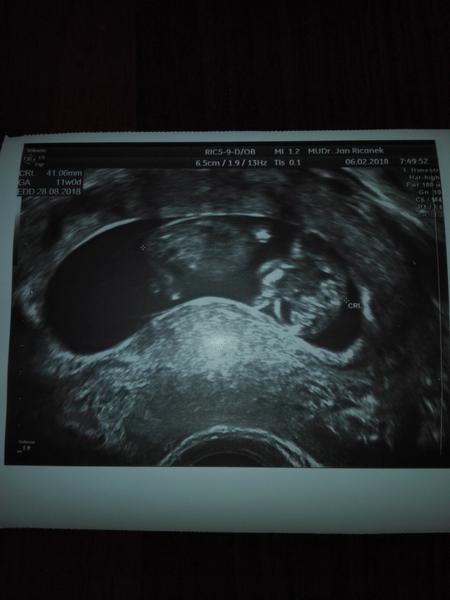

@pipinka Nádhera😍

@lucifervlkova to ano je neuvěřitelné jak prcek za 3 týdny vyrostl

@pipinka Ono je spíš neuvěřitelné,jak to vlastně vzniká😉.Je fajn,že roste.Je mu tam dobře😍

@lucifervlkova to s tebou naprosto souhlasím.už teď ho miluju